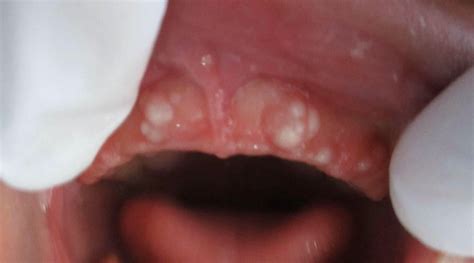

Las manchas blancas en las encías pueden ser motivo de preocupación para muchas personas. Aunque a menudo son benignas, en algunos casos pueden indicar problemas de salud más serios.

Una de las principales razones para la aparición de un recubrimiento blanco en las encías es la acumulación de placa bacteriana. La placa se forma cuando las bacterias en la boca se mezclan con saliva y restos de alimentos, creando una sustancia pegajosa que puede endurecerse y convertirse en sarro. Otra causa común es la candidiasis oral, una infección por hongos que puede causar la formación de manchas blancas en las encías, lengua y otras áreas de la boca.

- Si detectas parches o manchas blancas en las encías, en la base de la boca o en la parte interna de las mejillas, lo más probable es que padezcas leucoplasia. Pese a que se desconoce el origen de esta afección, se relaciona con el consumo de tabaco o alcohol, o con una higiene oral deficiente. En la mayoría de los casos, se trata de una enfermedad benigna. No obstante, en un pequeño porcentaje, puede ser un síntoma temprano de cáncer de boca, por lo que te conviene acudir al dentista para que te examine. Además de los parches irregulares de color blanco, la leucoplasia puede ocasionar partes engrosadas o endurecidas en la boca o bien lesiones de color rojo.

- Las aftas o llagas son úlceras que pueden aparecer en cualquier parte de la boca. Suelen resultar molestas y dolorosas al tacto, al hablar o al comer. Las llagas tienen el centro de color amarillo o blanco. Si aparecen en la parte inferior de la encía, hacen que se vea blanca.

- La candidiasis oral está ocasionada por un hongo que se desarrolla en la boca. Este mismo patógeno puede infectar otras partes del cuerpo y, de hecho, es más conocido por provocar infecciones vaginales en muchas mujeres. La candidiasis puede abarcar gran parte de la boca, incluso la lengua y las encías.

- El liquen plano oral es una enfermedad inflamatoria crónica no infecciosa que se presenta en forma de hilos blancos parecidos a una telaraña.